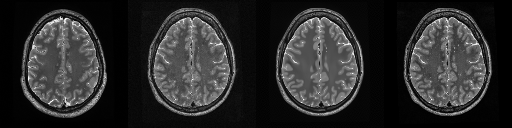

HCP T2w dataset

We utilize images from the publicly available Human Connectome Project (HCP) [51] T2-weighted (T2w) images dataset for the task of compressed sensing, which contains brain images from 47 patients. The HCP dataset includes cross-sectional images of the brain taken at different levels and angles.

Compressed sensing

We train a flow-based model from scratch on 10,000 randomly sampled images, utilizing the ncsnpp architecture [9] with minor adaptations for grayscale images. We employ compression rates , meaning . The measurement operator is given by a subsampled Fourier matrix, whose sign patterns are randomly selected. We evaluate our reconstruction algorithm’s performance on 200 randomly sampled test images.

We present the quantitative and qualitative results of compressed sensing in Tab. 1 and Fig. 4, respectively. As shown in Tab. 1, our method consistently achieves the best performance across varying compression rates . In Fig. 4, our method produces reconstructions that are more faithful to the original images, with fewer artifacts, leading to higher accuracy and clearer details.